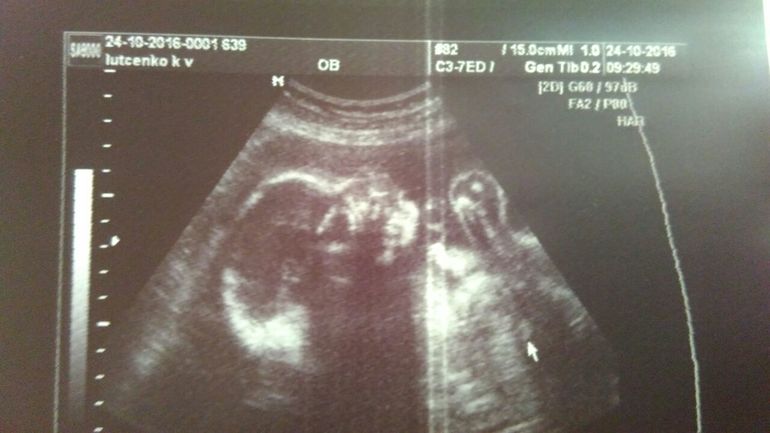

26 недель полных